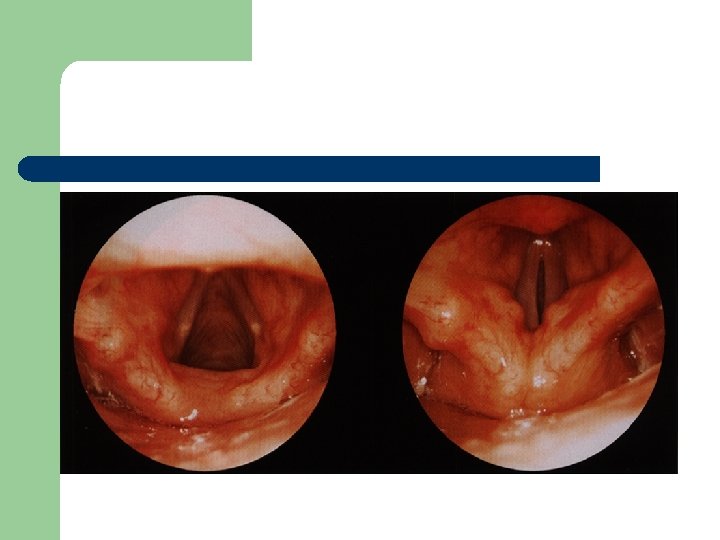

Dysfonie, dysodie l l Dysfonie je obecný termín pro všechny funkcionální poruchy tvorby a užití mluvního hlasu. Normální nález

Vývoj dětské chraptivosti l 1. 2. 3. 4. Průvodním jevem při dětské chraptivosti je pokašlávání a pochrchlávání. Nález na hlasivkách postupuje takto: Hyperemické (překrvené hlasivky, Hypertrofické, vřetenovité zduření, hlasivkový uzávěr je neúplný a hlas má dyšnou příměs, ventrikulární řasy se začínají vyklenovat Zpěvácké uzlíčky, nejčastěji na hranicích přední a střední třetiny hlasivek Atrofie hlasivek až s podélnou rýhou, při fonaci nedomykavost uzávěru.